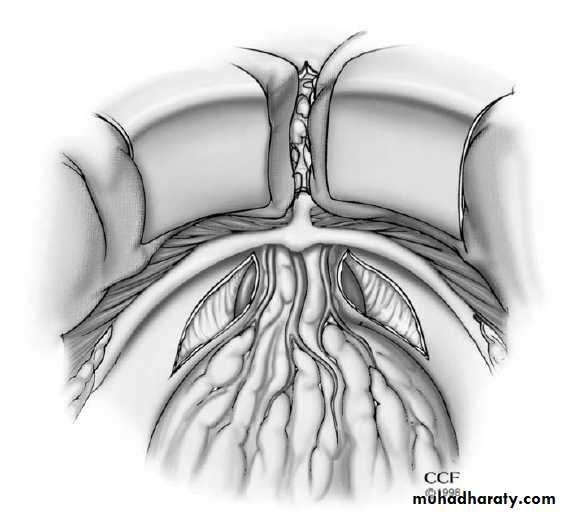

2. Radical prostatectomy

213. Radiation therapy

external beam therapybrachytherapy